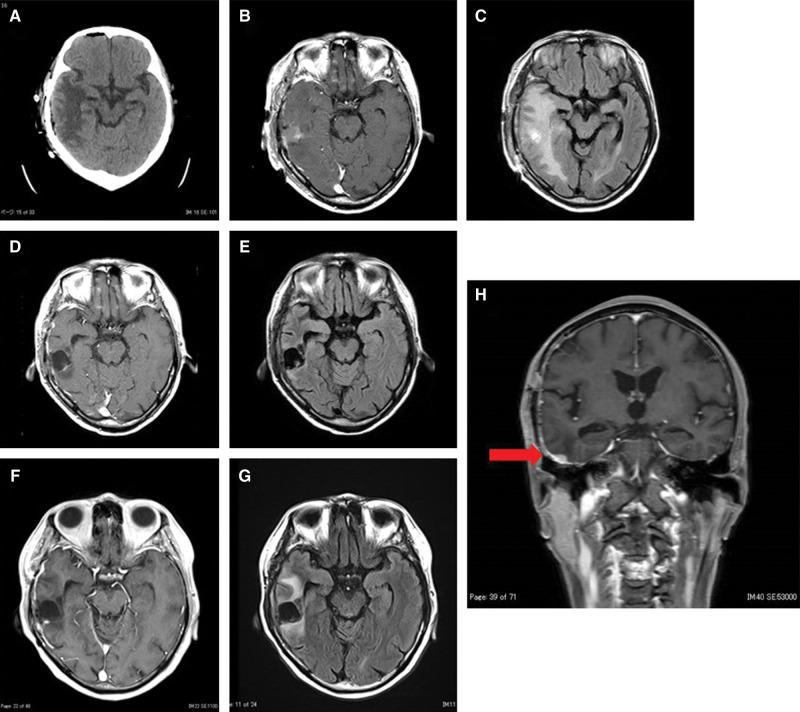

Extramammary Paget's disease (EMPD) is a rare form of neoplasm. Metastasis of EMPD to locations other than lymph nodes and intra-epithelial regions is rare; there are a limited number of case reports of metastases to the liver, lung, bone, and brain. We present a rare case of EMPD that metastasized to the brain and was treated with surgical resection. A 66-year-old man presented with a small palpable mass in the scrotum. After 5 years of observation, he was diagnosed with EMPD that metastasized to the lymph nodes and lung. Tumor resection and postoperative chemotherapy were performed. Six months after the last chemotherapy treatment, he presented with a right temporal lobe tumor and underwent surgical resection. Histopathological analysis revealed brain metastasis of EMPD. Three months after surgery, magnetic resonance imaging (MRI) showed local tumor recurrence, and intensity modulated radiation therapy (IMRT) (45 Gy/15 Fr) was performed. Although the metastatic brain tumor was well controlled, the primary tumor progressed. He was provided best supportive care and died 5 months after brain tumor resection. In this report, we present a rare case of brain metastasis of EMPD, treated with surgical resection, and histopathologically confirmed to be metastatic EMPD.

乳腺外佩吉特病(EMPD)是一种罕见的肿瘤形式。EMPD转移至淋巴结和上皮内区域以外部位的情况罕见;仅有少数关于转移至肝脏、肺、骨和脑的病例报告。我们报告一例罕见的EMPD脑转移病例,该病例接受了手术切除治疗。一名66岁男性阴囊出现一个可触及的小肿块。经过5年观察,他被诊断为EMPD伴淋巴结和肺转移。进行了肿瘤切除及术后化疗。最后一次化疗6个月后,他出现右侧颞叶肿瘤并接受了手术切除。组织病理学分析显示为EMPD脑转移。术后3个月,磁共振成像(MRI)显示局部肿瘤复发,遂进行调强放射治疗(IMRT)(45 Gy/15次分割)。尽管转移性脑肿瘤得到良好控制,但原发肿瘤进展。给予其最佳支持治疗,患者在脑肿瘤切除术后5个月死亡。在本报告中,我们呈现一例罕见的EMPD脑转移病例,经手术切除治疗,并经组织病理学证实为转移性EMPD。